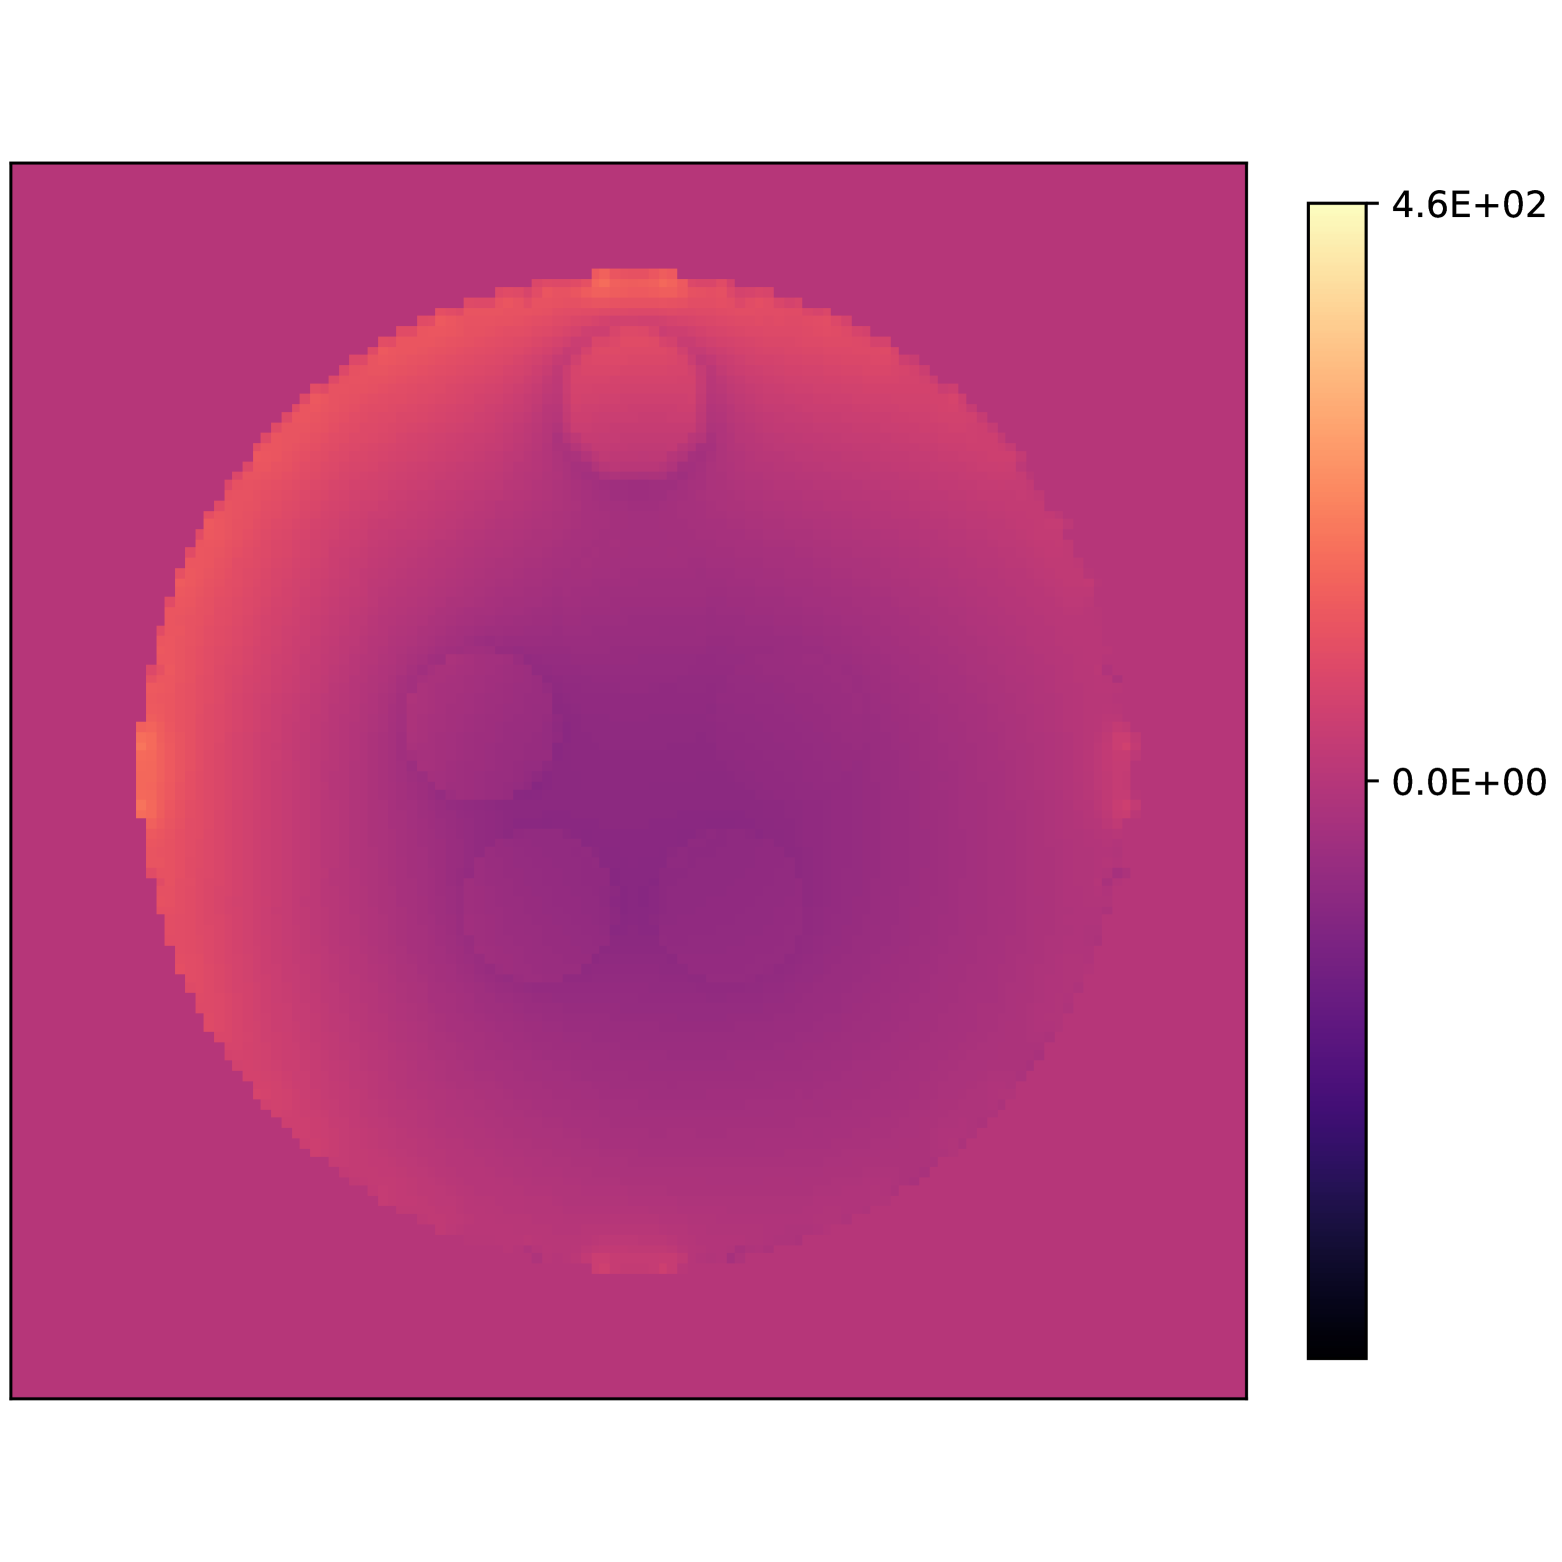

Our theoretical results show that generic concentrations and maps can be recovered exactly even when the fieldmap is not identifiable. To illustrate the impact of this fact, we perform a recovery experiment on a water (Fig. 2(a)), fat (Fig. 2(b)) and silicone (Fig. 2(c)) in silico phantom. The concentrations are all real. The values for the fieldmap and used to generate the signal are shown in Figs. 2(d) and 2(e). The echo times have the form where ms and ms with .

We solve (23) using projected gradient descent as initial iterate a vector with all components equal to one. Forward finite-differences were used to compute the gradient. The bound on the norm of the gradient is Hz at voxels with non-zero signal magnitude, and kHz at voxels with zero signal magnitude. This avoids imposing artificial constraints at voxels with no signal. The step size used is and the termination conditions

In Figs. 2(f), 2(g) and 2(h) show the recovered concentrations of water, fat and silicone, and Fig. 2(j) shows the recovered . These recovered quantities are all qualitatively similar to their true values. In contrast, Fig. 2(i) shows the recovered fieldmap, which differs from its true value. By comparing the errors in the recovered concentrations, we see that they are within a reasonable accuracy except in regions with a large magnitude for the fieldmap gradient, indicating a bound that is too small (Figs. 2(k), 2(l) and 2(m)). A similar behavior is seen in the recovered (Fig. 2(o)). The error for the recovered fieldmap tends to be larger outside the area of the phantom (Fig. 2(n)).